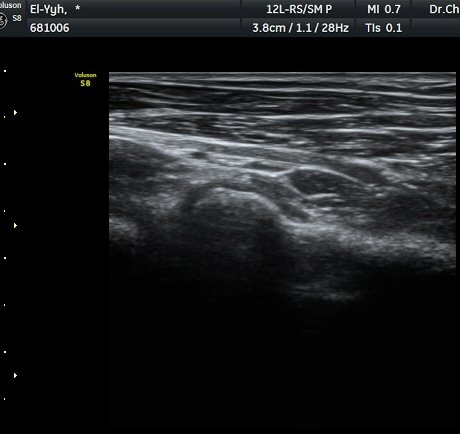

ÃÊÀ½ÆÄ °Ë»ç